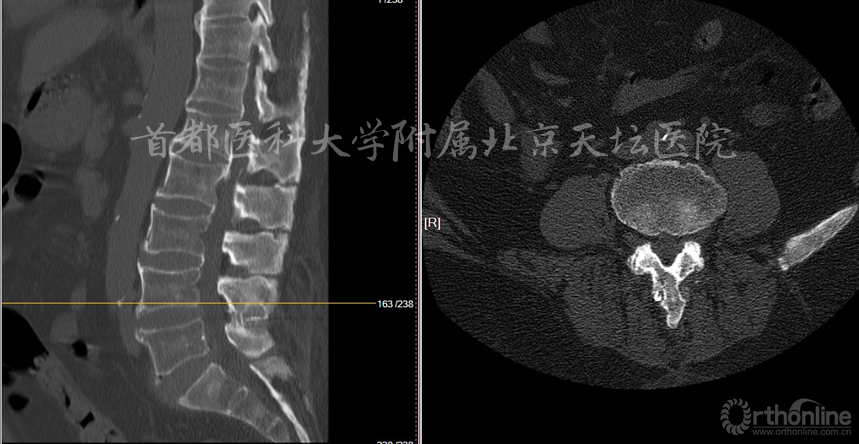

影像资料:

诊断:

• 腰椎管狭窄症(双侧神经根管狭窄)

• 棘突间植入物术后(Wallis)

• 棘突骨折

针对此病例,各位专家的讨论焦点主要落在棘突间植入物的疗效究竟如何上。天坛医院刘宝戈教授针对这个病例指出,患者曾在外院行棘突间植入物手术,术后不久再次出现症状,翻修手术如何进行?这需要细致的考量。针对该例老年患者,他们最终选择了微创的治疗方式,基于术前精确责任节段的定位,术后疗效满意。